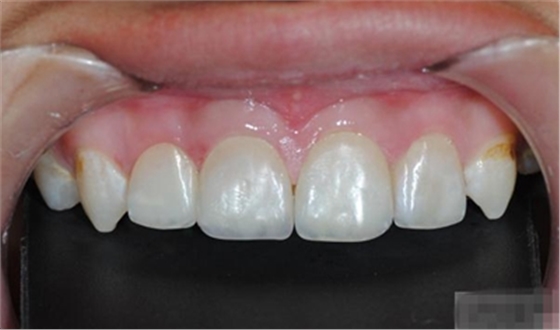

充填初步完成

【初步修整】

對(duì)于唇面,首先使用火焰狀車針進(jìn)行修整,一般不使用輪狀車針修整線角

微細(xì)的表面結(jié)構(gòu)最后使用鎢鋼拋光車針成形的。

修整完成